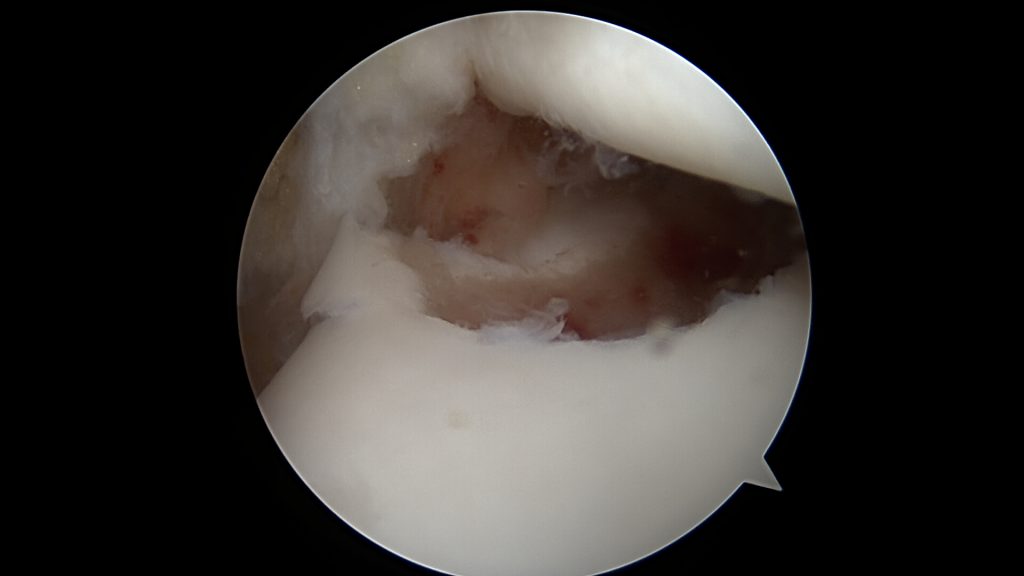

Leczenie operacyjne polega na oczyszczeniu oraz odświeżeniu dna ubytku oraz wypełnieniu go materiałem Hyalofast, dedykowanym do uszkodzeń chrzęstno-kostnych. W niektórych przypadkach (młody wiek oraz duża wielkość fragmentu) możliwe jest ponowne przytwierdzenie wydzielonego fragmentu chrzęstno-kostnego OCD, jeśli nie uległ on wcześniej zniszczeniu.

Po wypełnieniu miejsca ubytku implantuje się komórki macierzyste, które na bazie usieciowanego kwasu hyaluronowego wytwarzają regenerat chrzęstny.